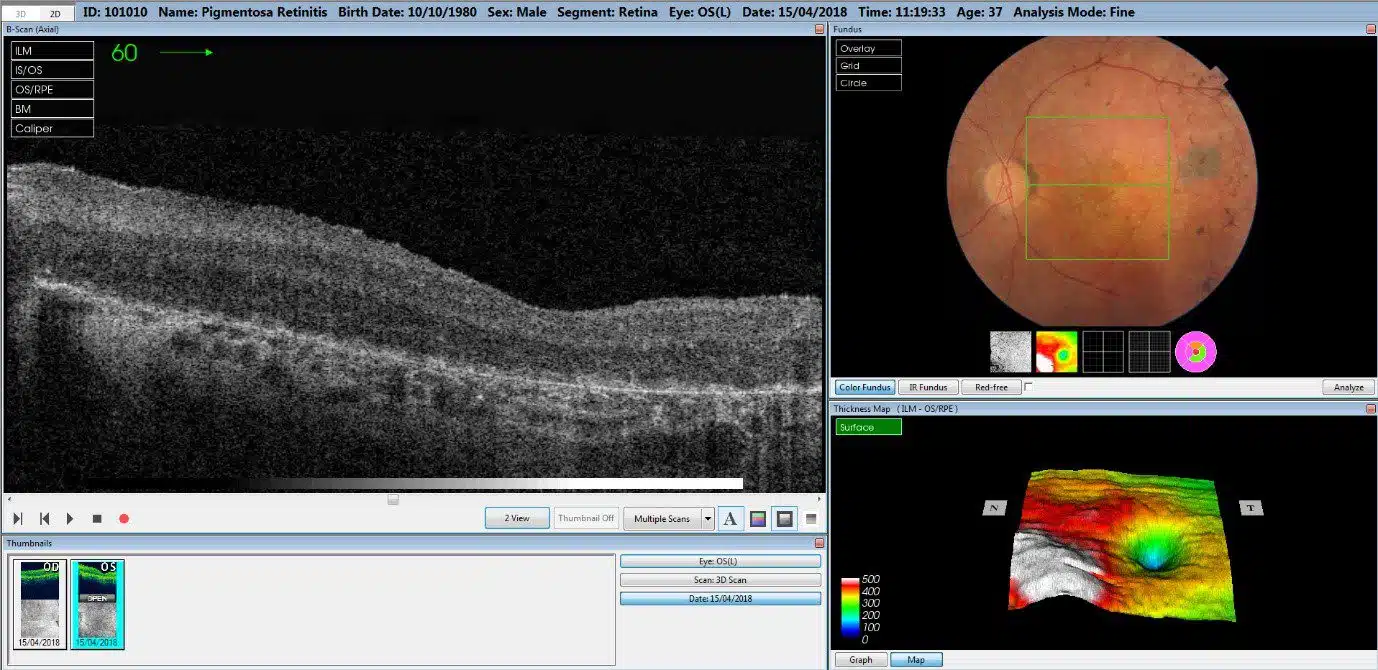

You happily go along to the optometrist, feeling good about life. Then comes the bolt out of the blue when the OCT scan reveals a problem. You need to be referred to an ophthalmologist.

Your optician will have been thorough and done his or her job, studying the photo of the back of your eyes. Something isn’t right with your vision and it is in a degenerative state. You are facing low vision or possible blindness.